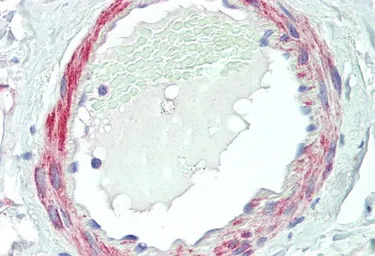

IHC-P analysis of human prostate using GTX10099 VPS35 antibody, C-term.

Antigen retrieval : citrate buffer pH 6

Dilution : 5μg/ml